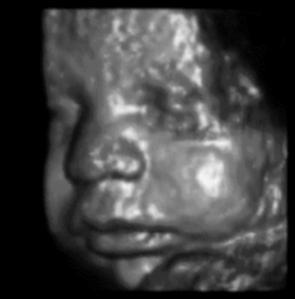

The same technique can be used to probe biological tissues: by determining the time delay from pulse emission to echo detection, one can determine the depth of reflecting tissue layers. Furthermore, by knowing the acoustical impedance (discussed in Topic 3) of each layer, we can even determine the percent of the ultrasound intensity that is reflected by each of those layers. The reflectivity aids us in characterizing which type of tissue is reflecting the ultrasound waves. A typical ultrasound scan is shown below in Figure 4.

(a)A typical 2D real-time image obtained during an ultrasound scan.

(b)A 3D reconstruction derived from multiple 2D scans

Figure 4:Examples of ultrasound imaging.